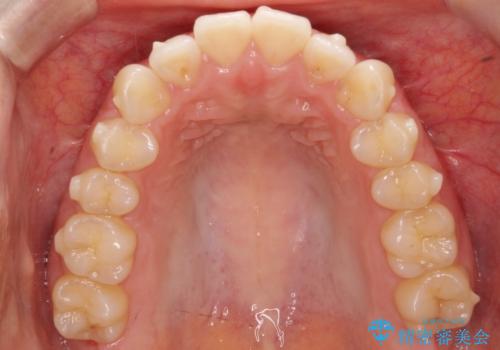

下顎前歯の叢生を短期間で改善

- 患者様は、下顎前歯のガタガタ(叢生)の改善を希望して来院されました。診断の結果、非抜歯で治療可能であると判断し、透明で目立たないインビザラインを使用する矯正治療計画を立案しました。短期間での治療を希望されていたため、IPR(歯間削合)を併用してスペースを確保しながら、効率的に歯を並べることを目指しました。

治療では、インビザラインを用いて計画的に歯を移動させ、短期間での歯列改善を実現しました。IPRを行うことで、抜歯をせずに必要なスペースを確保し、歯列全体を整えました。治療中は、装置の適切な装着時間を守ることが重要であり、患者様にも継続的な協力をお願いしました。また、歯肉や歯根への負担を最小限に抑えるため、歯の移動を慎重に管理しました。結果として、短期間で下顎前歯の叢生を改善し、自然な見た目と機能性を兼ね備えた歯列を実現できました。